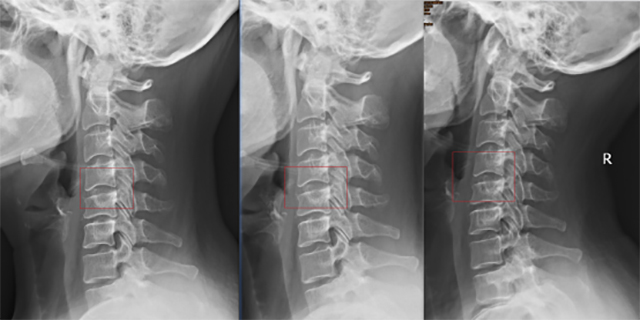

康复治疗前 康复治疗6周 康复治疗12周

随即,朱女士在西南医科大学附属中医医院针灸·推拿·康复科蒋奎娄治疗师的阶段性治疗下,进行了12周的康复训练,颈椎曲度才逐渐好转。

判断颈椎曲度通常借助X光片观察,主要有C型、Ƨ型I型和ɔ型。你属于哪一种?

正常C型 异常Ƨ型 异常I型 异常ɔ型

正常颈椎有一个“C”型曲度,颈椎反弓通常是颈椎病、颈椎劳损的早期表现,是日常生活、工作中长期保持一些不良姿势导致,如低头伏案看书、看手机、看电脑、半躺沙发看电视,并缺少应有的颈部锻炼。